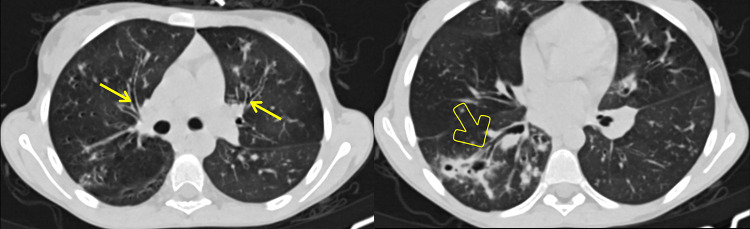

囊性纤维化(CF)是一种多系统疾病,是由于第 7 号染色体上的 CF 跨膜传导调节器(CFTR)基因突变导致的常染色体隐性先天性遗传。由于该病被认为是高加索儿科人群的疾病,或者由于缺乏认识,像我国这样的发展中国家很少考虑该病。本病例报告是埃塞俄比亚(也可能是东非)报告的首例囊性纤维化病例,患者是一名 17 岁女性,在对其腹部和胸部进行 CT 扫描后确诊患有该病。由于她长期咳嗽,最初被误诊为肺结核(TB)并接受治疗。也许是由于流行病学证据,在埃塞俄比亚,几乎所有慢性咳嗽伴有肺实质纤维支气管扩张病变的病例都被顽固地归咎于肺结核(TB)。一旦对这些病人做出结核病诊断,他们的诊断就会陷入结核病再感染、复发或耐药的怪圈,随后又要接受多个阶段的抗霉菌药物治疗。这可能会导致危险的影响,包括不必要的长期抗霉菌治疗、产生耐药性的可能性以及与管理不当有关的患者发病率。该患者的胸部和腹部 CT 结果,包括支气管扩张、肝脂肪变性、胰腺脂肪瘤、微小胆囊和近端结肠壁增厚,导致了 CF 的诊断。这篇文章介绍了该地区第一例有记录的 CF 病例,旨在提醒临床医生和放射科医生也要考虑像 CF 这样可能 "罕见 "的疾病,而不是把每一次慢性咳嗽都归咎于肺结核,并强调了腹部 CT 特征在 CF 诊断中的重要性。

Cystic fibrosis (CF) is a multisystem disorder that occurs as a result of autosomal recessive congenital transmission of CF transmembrane conductance regulator (CFTR) gene mutation on chromosome 7. Because it is considered a disease of the Caucasian pediatric population or due to lack of awareness, it is rarely considered in developing countries like ours. This case report presents the first case of cystic fibrosis ever reported in Ethiopia and possibly East Africa, that of a 17-year-old female diagnosed with the disease following a CT scan of her abdomen and chest. She was initially misdiagnosed and treated for tuberculosis (TB) as she was a chronic cougher. Perhaps due to epidemiological evidence, there is an obstinate tendency of blaming tuberculosis (TB) for almost every case of chronic cough with fibro-bronchiectatic lung parenchymal changes in Ethiopia. Once a diagnosis of TB is posted on such patients, their diagnosis remains in the circle of TB reinfection, relapse or resistance, followed by multiple phases of anti-mycobacterial drugs. This could lead to hazardous implications, including unnecessary prolonged anti-mycobacterial treatments, possibility of developing drug resistance, and mismanagement-related patient morbidity. This patient's chest and abdominal CT findings, including bronchiectasis, hepatic steatosis, pancreatic lipomatosis, micro-gallbladder and proximal colonic wall thickening, led to the diagnosis of CF. This article, presenting the first documented case of CF in the region, is meant to be a helpful reminder for clinicians and radiologists to also consider presumably "rare" illnesses like CF rather than blaming TB for every chronic cough and highlights the importance of abdominal CT features in the diagnosis of CF.